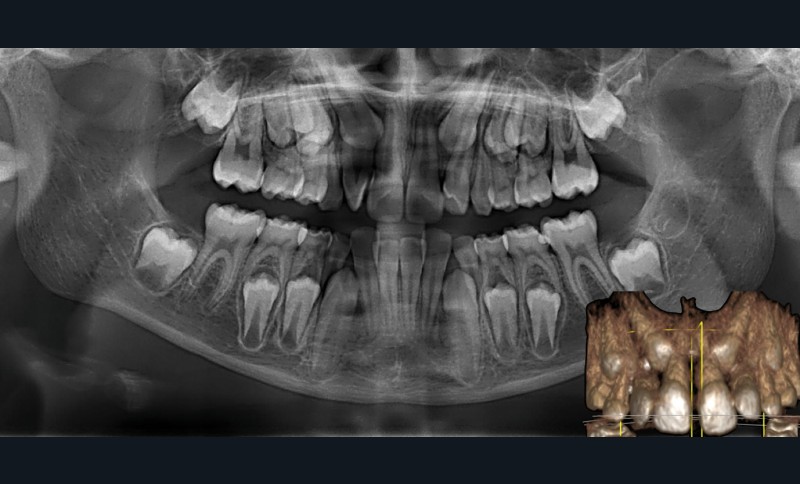

La patiente consulte à l’âge de 9 ans pour la malposition de ses incisives latérales maxillaires. Elle présente une occlusion de Classe I bilatérale sur un schéma normodivergent avec une dysharmonie dento-maxillaire en denture mixte. À l’arcade maxillaire, elle présente une endoalvéolie avec rotations mésiopalatines de 16 et 26.

Sur la radiographie panoramique, on observe une transposition des canines maxillaires en place d’incisives latérales, au contact des racines de 11 et 21.